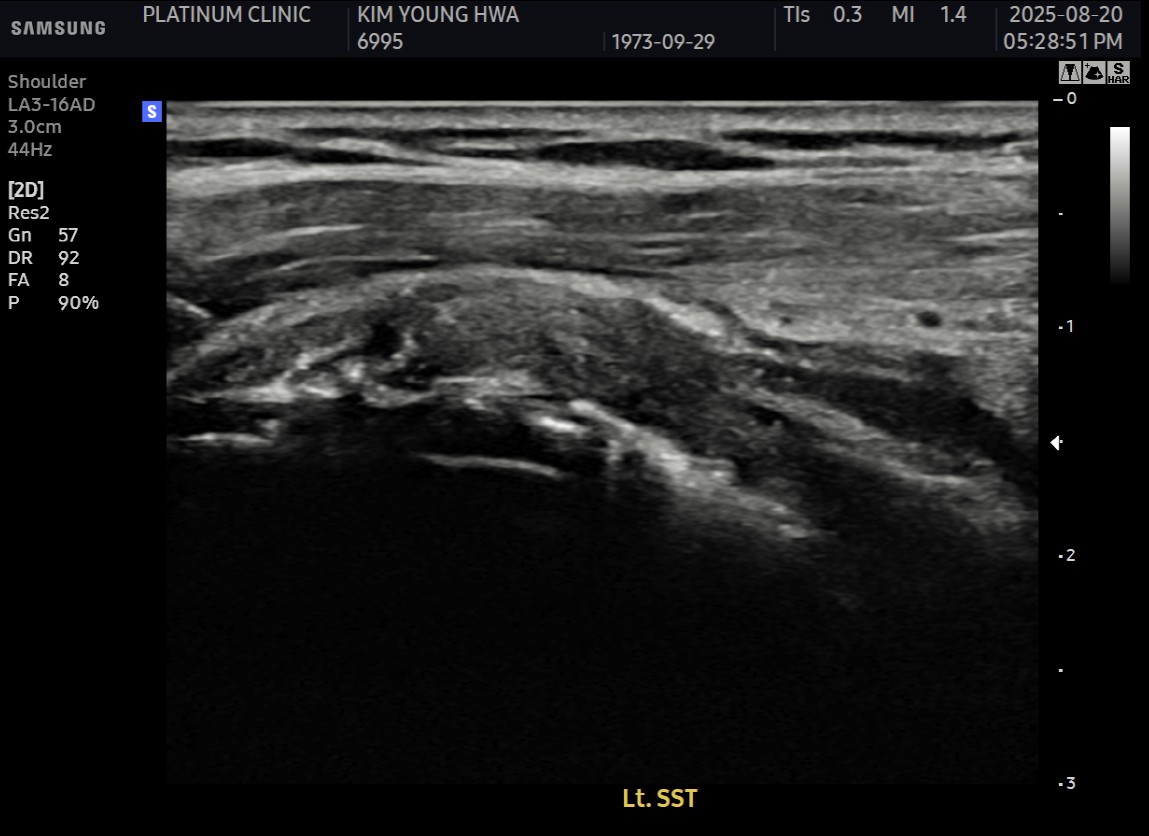

MRI와 초음파 검사 결과:

진단 결과:

- ✓관절면측 부분파열: 약 50%

- ✓점액낭면측 부분파열: 약 35%, 인대 얇아짐 동반

- ✓25년간 반복 사용으로 인한 퇴행성 변화 동반

양쪽 모두 손상된 복합 파열이었습니다.

- ✓관절면측: 봉합 부위 안정적 유지

- ✓점액낭면측: 인대 두께 4.8mm → 6.5mm (1.7mm 증가)